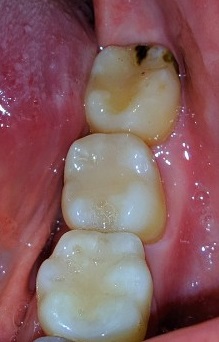

Добрый вечер! Подскажите пожалуйста можно ли спасти зуб. К какому специалисту обращаться по данному вопросу ?

Нажмите на изображение для увеличения

Название: 123.jpg

Просмотров: 178

Размер:	19.6 Кб

ID:	13135919

Вложение 13135919

...потраченные средства и время на спасение этого зуба в итоге могут совсем не соответствовать ожиданиям в достижении конечного результата...

...если учитывать только обозримый участок (хронический процесс), то срочности большой нет, 1-2 мес. погоды не сделает. Снимок бы дал более полный прогноз. Лечить можно и нужно.

Спасибо за Ваше мнение. Удалить всегда можно успеть. Просьба другим стоматологам посоветовать к кому можно обратиться в Одессе по данному вопросу (очно).Нажмите на изображение для увеличения

Можно, конечно. Главное - не затянуть до момента, когда придётся ещё и 5-й зуб удалять. Ситуация не очень благоприятная, увы.

Я, конечно, не врач, просто поделюсь - ситуация была точно такая же на нижней 6ке. Тоже сразу советовали удалить, но пыталась спасти до последнего. Лечили, время тратили, деньги тратили. Все равно в итоге киста (чуть было и на соседний зуб не пробралась) - воспаление - флюс-удаление. Потом еще ждала пока восстановится костная ткань. Надо было сразу удалять и имплантировать